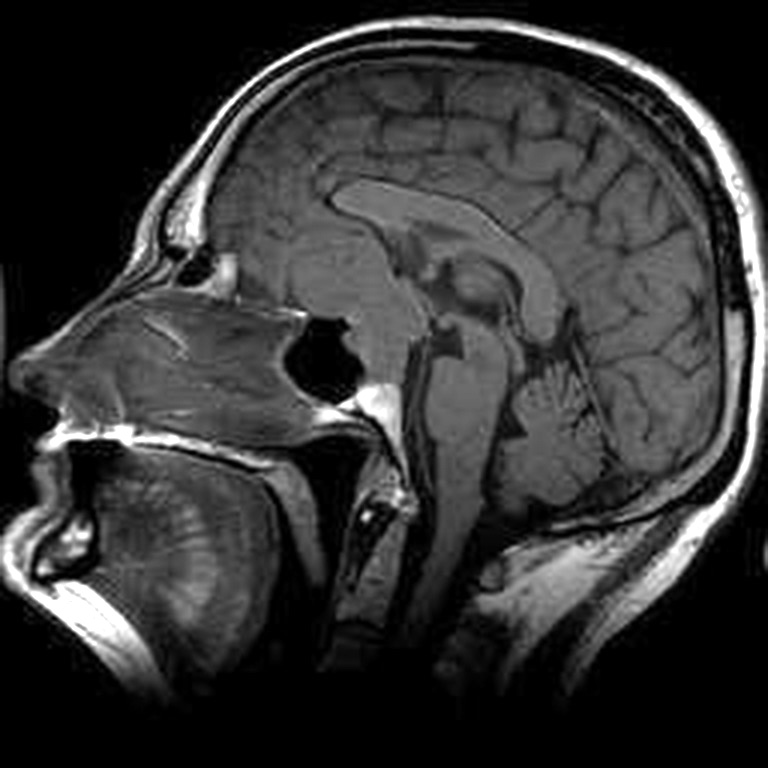

Fig. 2. Patient P., 64 years old, HIPA with suprasellar extension, central chiasmal position. Brain MRI: A – coronal projection; B – sagittal projection

A B

Fig. 4. Patient M., 54 years old, HIPA with antesellar extension, posterior chiasmal position. Brain MRI: A – sagittal projection; B – coronal projection